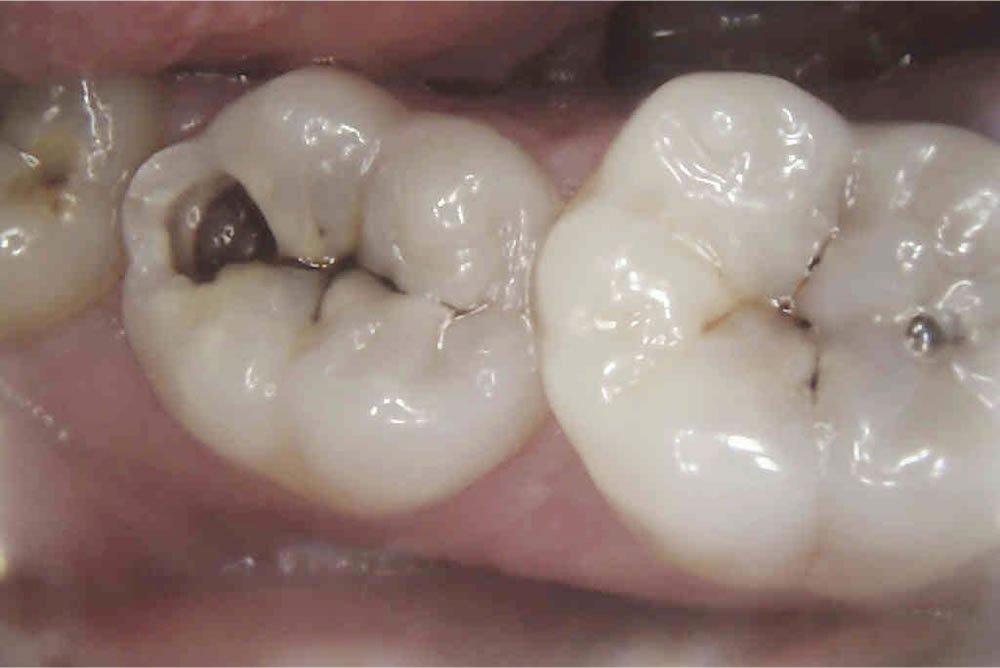

ジルコニアインレーを用いた虫歯治療の症例

虫歯治療後に審美性・耐久性の高いジルコニアインレーで咬み合わせを修復した症例をご紹介致します。

| 年齢・性別 | 30代 女性 |

|---|---|

| 治療期間 | 約2週間 |

| 治療回数 | 3回 |

| 治療費 | ジルコニアインレー 88,000円(税込) |

| リスクなど | ・過度な咬合力により、つめ物が破損したり、外れたりすることがあります。 ・素材の厚みがあるため、歯の切削量が少し多くなります。 |